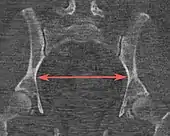

| Interspinous distance | ![]() |

The line between the closest bone points of the ischial spines | 9.5 to 11.5 cm.[6] | |